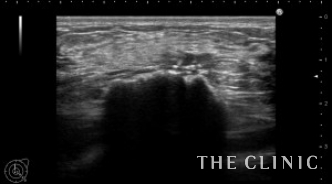

触診では両側乳房にしこりを触れ、エコーでは2cmを超える石灰化したしこりを認めました。何度か注射針で吸引しているのでしこりは辺縁不整で周囲組織と癒着している状態です。